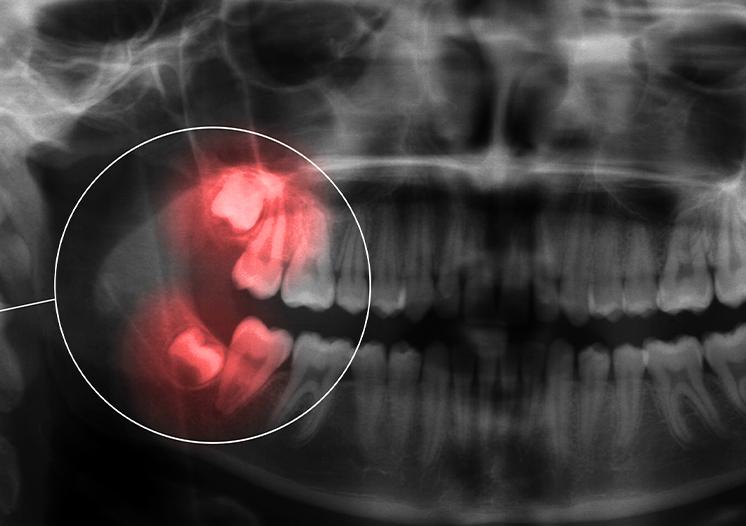

Before recommending wisdom teeth removal, we look at how your teeth are positioned and how they may affect your oral health over time. This may include reviewing digital X-rays, looking at how the teeth are developing, and talking through any symptoms you may be experiencing.

● Impacted teeth that remain under the gums or bone